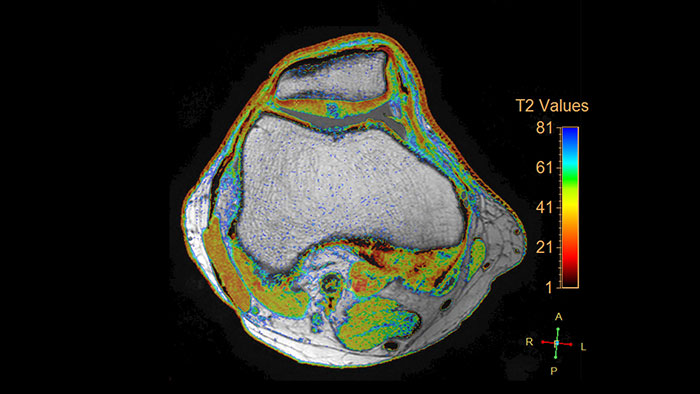

MR Cartilage Assessment

Visualize cartilage structures

Enables the visualization of cartilage structures integrated with color-coded T2 maps. Positioning of cartilage-shaped, layered region of interest is used to assess variation of T2 values across the cartilage depth to determine the degradation of the cartilage.

• The MR Cartilage Assessment application features a task-guided workflow for the quantitative analysis of T2 relaxation time to support cartilage assessment and disease status.

• The application provides segmentation tools, allowing measurements of cartilage layers and segments.

• T2 values are numerically and graphically displayed per layer and segment.